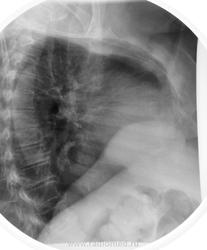

Пацинтка 60 лет. Остро возникшая нижняя параплегия. (3 дня). Рентгенограммы выполнены в положении лежа.

По нижнему заднему средостению начал бы с глотка бария...

Ещё предложение: дать барий и исключить аксиальную грыжу.

yes. Частично внутригрудной желудок

Несомненно сочетание патологии.

К позвонкам стоит присмотреться

Ретроспективно зная, что это такое, ещё раз просматривая снимки , по боковой проекции  видно просветление  на фоне тени, с учётом  картины по прямой проекции, можно было бы и догадаться с чем имеем дело, но что-то не сработало в черепной коробке (видимо правльно говорят военные, что голова -это кость). Если серьёзно, такая картина нечасто встречается и как понимать термин-Частично внутригрудной желудок?Есть укорочение пищевода или пищевод нормальной длины ( тогда это будет фиксированная грыжа пищеводного отверстия диафрагмы).

Литический метастаз Th11.

Рак щитовидной железы. Диагноз верифицирован гистологически. Ответ биопсии получен вчера и из железы и из позвонка